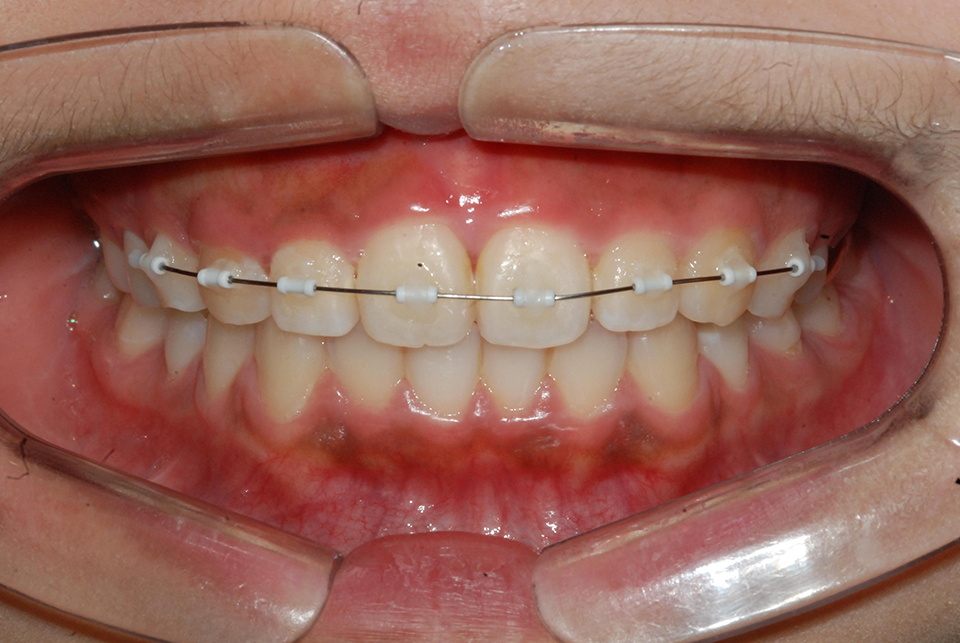

¼ºÀå±â¿¡ ÁÖ°ÆÅÎÀ̳ª ¹«ÅÎ, ¾È¸éºñ´ëĪ µîÀÇ °ñ°ÝÀû ¹®Á¦¸¦ Áö´Ï°í ÀÖ´Â °æ¿ì Ä¡¿±³Á¤¿¡ ¾Õ¼ ¼ºÀåÁ¶Àý Ä¡·á¸¦ ÇÊ¿ä·Î ÇÏ°Ô µË´Ï´Ù(±×¸²2). Åë»ó 2³â ³»¿ÜÀÇ Àû±ØÀû Ä¡·á¸¦ ¿ä±¸ÇÏ´Â °æ¿ì°¡ ÀϹÝÀûÀ̳ª ºÎÁ¤±³ÇÕÀÇ ½Éµµ³ª ³À̵µ¿¡ µû¶ó ±â°£ÀÌ ¸¹Àº ºÎºÐ ´Þ¶óÁú ¼ö ÀÖ½À´Ï´Ù. ÀÌ·¯ÇÑ Ä¡·á´Â Àǻ簡 Á÷Á¢ Ä¡¾Æ¸¦ ¿òÁ÷¿© Á¶ÀýÇÏ´Â ¹æ¹ýº¸´Ù´Â ȯÀÚÀÇ ÇùÁ¶¸¦ ¿ä±¸ÇÏ´Â Àåġġ·á°¡ º¸ÆíÀûÀ̱⠶§¹®ÀÇ È¯ÀÚÀÇ ÇùÁ¶µµ°¡ Ä¡·á±â°£ÀÇ °áÁ¤Áþ´Â °¡Àå Áß¿äÇÑ ¿ä¼ÒÀÔ´Ï´Ù. ¼ºÀåÀÇ ¼Óµµ ¶ÇÇÑ Áß¿äÇÏ´Ù°í ÇÒ ¼ö Àִµ¥ ÅÎÀÇ ¼ºÀåÀº ŰÀÇ ¼ºÀå¿¡ ºñ·ÊÇÏ¿© ¹ß»ýÇÏ´Â »ý¸®Àû º¯ÈÀ̱⠶§¹®ÀÔ´Ï´Ù. ¶ÇÇÑ ¼ºÀåÁ¶ÀýÄ¡·á´Â ÀÏ´Ü °³¼±ÀÌ µÇ¾ú´Ù°í ÇÏ´õ¶óµµ ÀÜ¿©¼ºÀå¿¡ µû¸¥ Àç¹ß °¡´É¼ºÀÌ ÀÖÀ¸¹Ç·Î ¼ºÀåµÐȱ⠱îÁö ¼ºÀå±â Àü¹Ý¿¡ °ÉÄ£ Ä¡·á-°üÂûÀÌ ¿ä±¸µË´Ï´Ù.

| | ±×¸²2 |